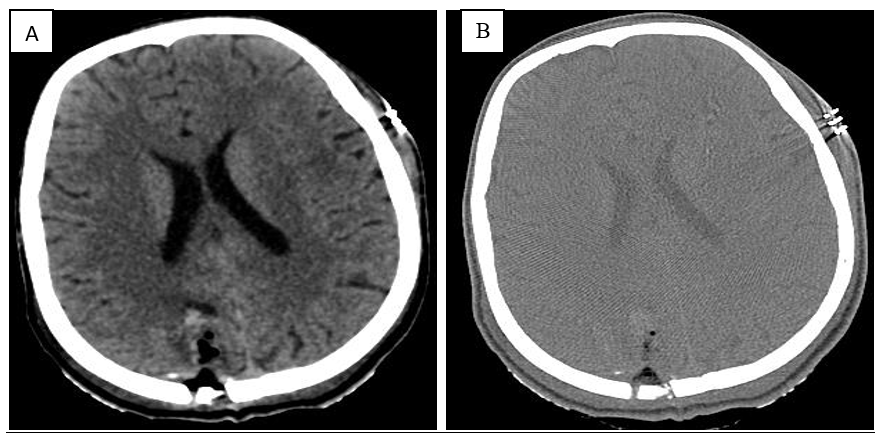

MRI study at admission revealed an ill-defined, irregular, heterogenous, nonenhancing, predominantly cortical-based bubbly appearing cystic lesion involving the right posterior parietal lobe with no perilesional edema – findings that were compatible with a diagnosis of DNET – Type 2 (Figure 1-7).1

Figure 6 A) Brain window B) Bone window: Craniotomy defect noted in right parietal bone in the parasagittal region. Near complete resection of cystic mass noted. Post operative changes showing air foci and few hemorrhagic foci and minimal pneumocephalus are noted in the region of operated tumour bed.